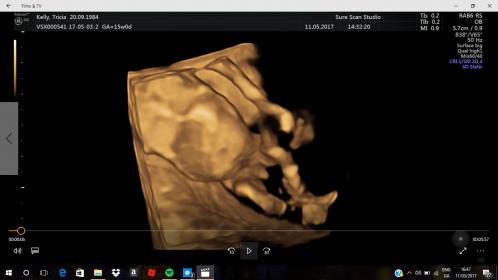

Hmmm. I don't see a clear scrotum. I don't see anything that makes me think of an obvious penis. I think this is your girl, but I would wait until your next scan to buy anything to be sure.

Oh, and 3D scans are notorious for distorting images. I was told by the techs at my hospital that to not have gender revealed on a 3D scan for this very reason.